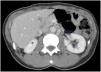

During follow-up, a possible para-aortic tumour recurrence and a lymphadenopathy suspected of malignancy were observed (Fig. 1). A PET-CT scan demonstrated a doubtful uptake in the retroperitoneal lesion (Fig. 2). In view of a possible tumour recurrence, the patient was assessed in conjunction with Internal Medicine. She had three major criteria for tuberous sclerosis (acoustic neurinoma, pulmonary lymphangioleiomyomatosis and retroperitoenal PEComa) and it was decided to start treatment with m-TOR inhibitors (sirolimus 2mg daily). Sirolimus levels are monitored every two months. After 3 months, a follow-up CT scan showed radiological improvement of the lesions with a decrease in the size of the mediastinal and retroperitoneal adenopathies described. (Fig. 3). At the present time, the patient has no signs of recurrence in control imaging tests and continues treatment with sirolimus, very well tolerated and without relevant adverse effects.